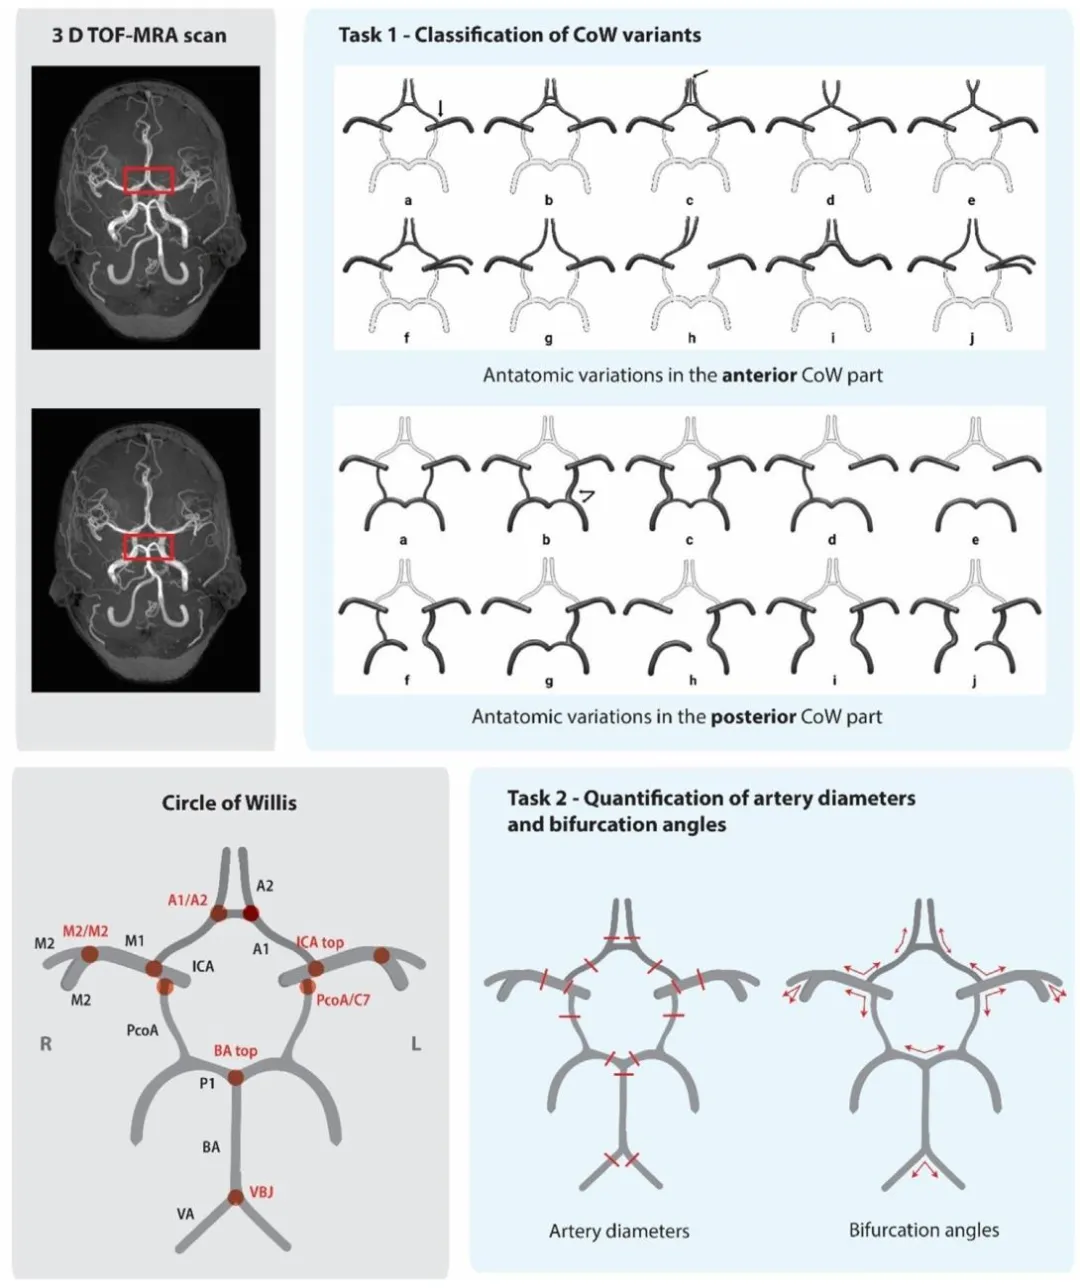

Fig. 2. Overview of tasks in the CROWN challenge. Upper left: 3 D TOF-MRA scan used as the input for both tasks. Red boxes indicate the anterior (upper) and posterior (lower)CoW part. Lower left: Schematic representation of the circle of Willis (CoW), with arteries denoted in black and bifurcations in red. A1 = A1-segment of the anterior cerebralartery (ACA), A2 = A2-segment of the ACA, M1 = M1-segment of the middle cerebral artery (MCA), M2 = M2-segment of the MCA, ICA = internal carotid artery, PcoA = posteriorcommunicating artery, P1 = P1-segment of the posterior cerebral artery, BA = basilar artery, VA = vertebral artery, C7 = C7-segment of the ICA, VBJ = vertebrobasilar junction.Upper right: Classification of CoW anatomical variants according to Lippert’s system, figure adapted from (Ophelders et al., 2024). Lower right: Quantification of major CoW arterydiameters and bifurcation angles

图2. CROWN挑战赛任务概述 左上:作为两项任务输入的3D TOF-MRA扫描图像。红色方框分别指示Willis环(CoW)的前部(上方)和后部(下方)。 左下:Willis环的示意图,其中动脉以黑色标注,分叉处以红色标注。A1=大脑前动脉(ACA)A1段,A2=大脑前动脉A2段,M1=大脑中动脉(MCA)M1段,M2=大脑中动脉M2段,ICA=颈内动脉,PcoA=后交通动脉,P1=大脑后动脉P1段,BA=基底动脉,VA=椎动脉,C7=颈内动脉C7段,VBJ=椎基底动脉连接处。 右上:根据Lippert分类系统对Willis环解剖变异的分类,图改编自(Ophelders等,2024)。 右下:Willis环主要动脉直径和分叉角度的量化。